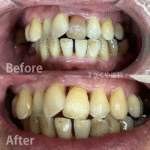

インプラント治療例(70代 女性)_0004

インプラント治療例 「下の入れ歯が合わない」ということでご来院いただきました。インプラント治療で快適に噛めるようになりました。 レントゲン画像 実際の見た目の写真